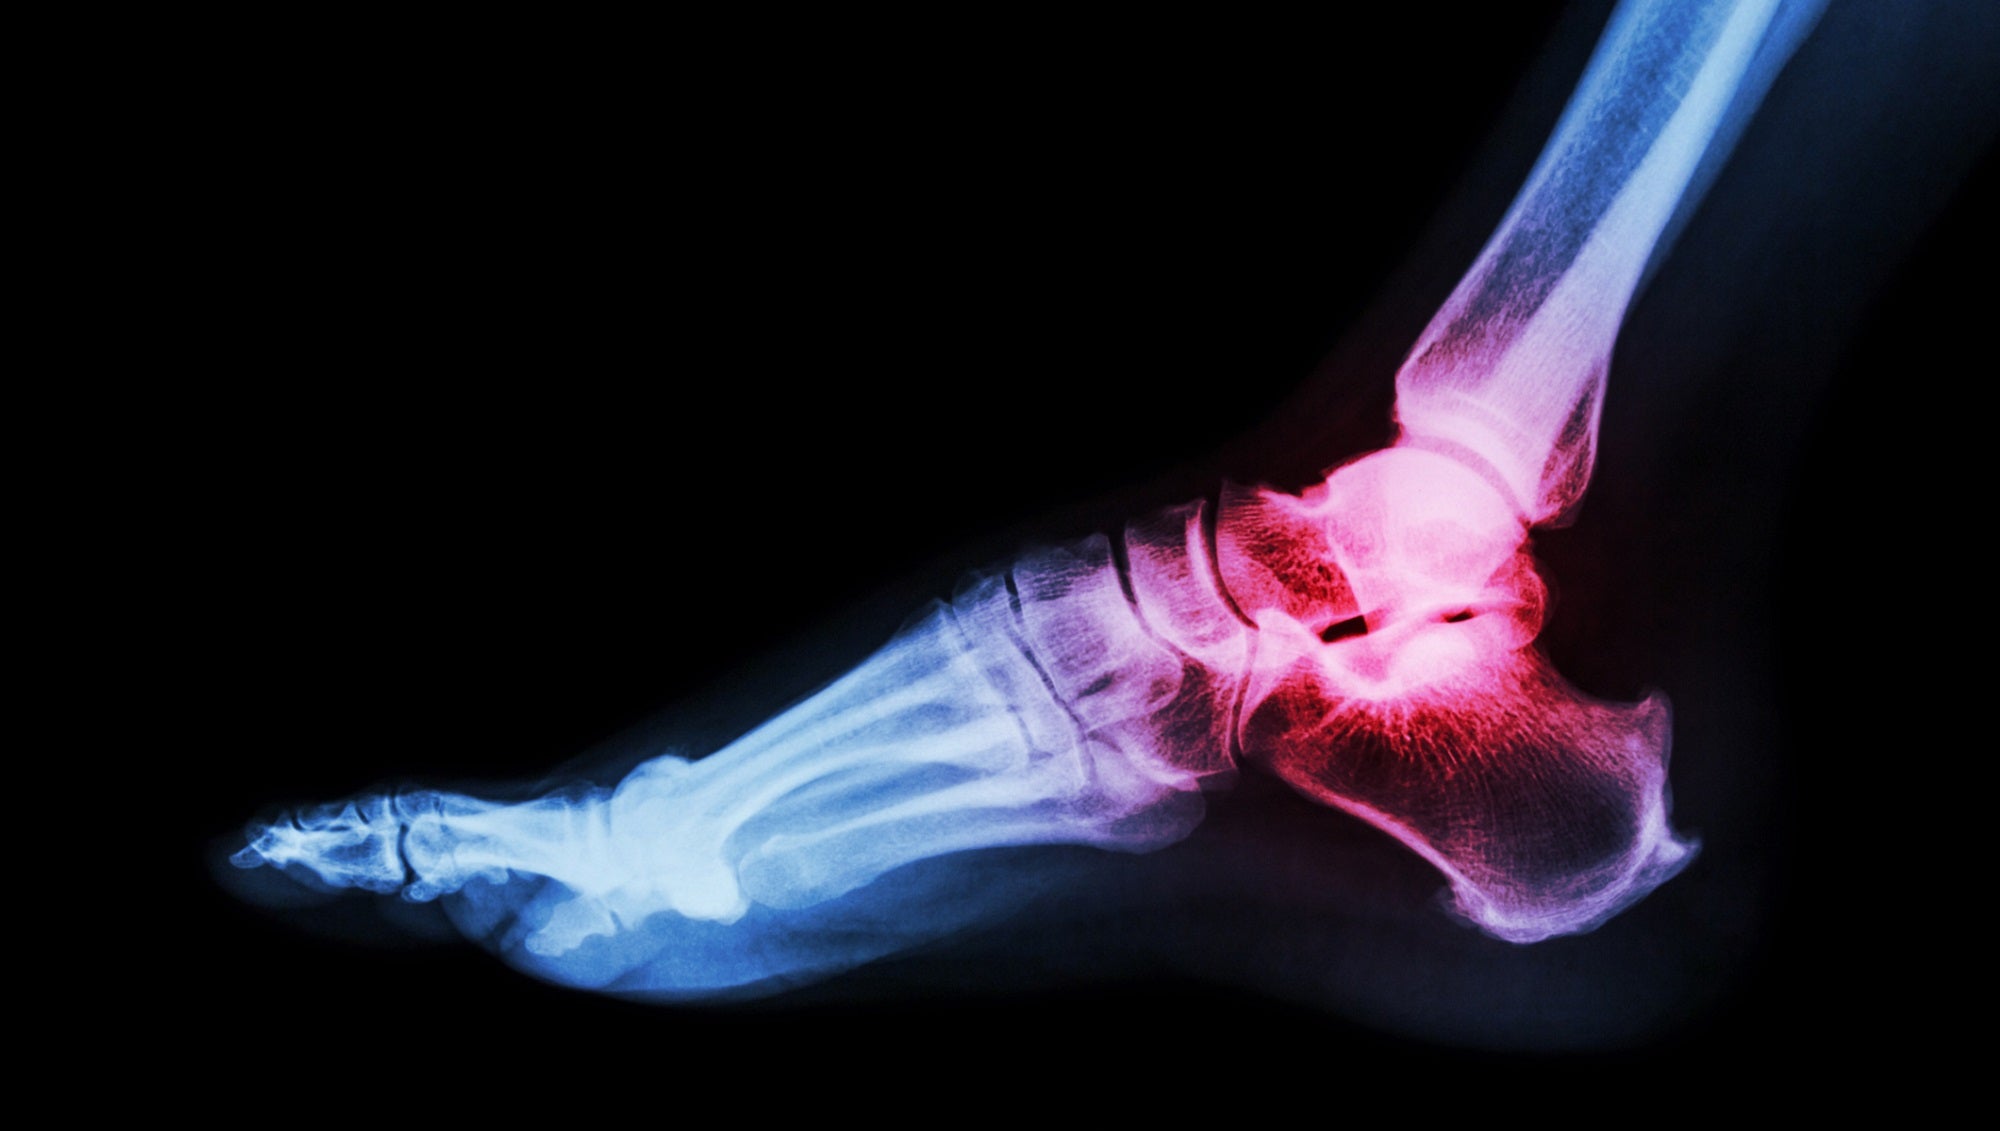

Select a video below to learn more about the procedures we perform at the Saint Alphonsus Coughlin Foot & Ankle Clinic. These videos give additional detail on not only our specialized procedures but also conditions that we treat and how these procedures lead to lasting recovery from pain.